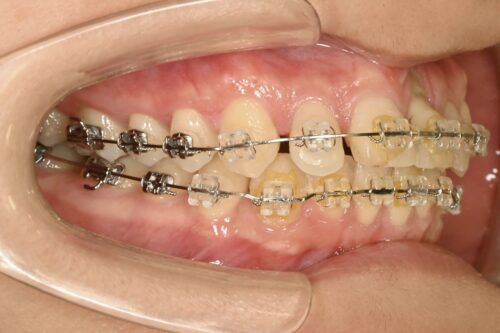

矯正治療開始

ワイヤーをつけて、歯の位置を上下とも動かします。

もともと出っ歯になってしまっていた上の歯も、まっすぐ向き直してきました。

矯正治療においても、出っ歯の上の歯だけを引っ込めたいと思っても、

下の歯がじゃまして動かないので、上下で治療する必要があるのです。